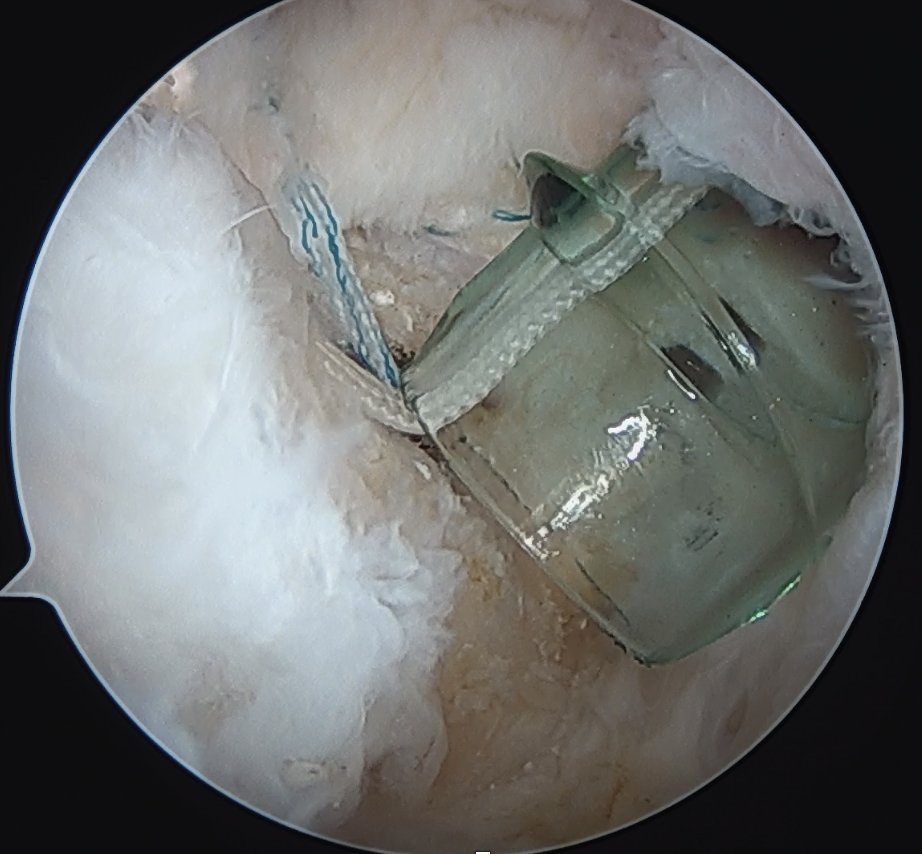

Trans-osseous equivalent / suture bridge

- cross sutures from medial row to lateral row

- increase contact between cuff and footprint

Arthroscopic Suture Bridge Cuff Repair

Double row / suture bridge

- use medial row sutures

- secure in knotless lateral row anchors